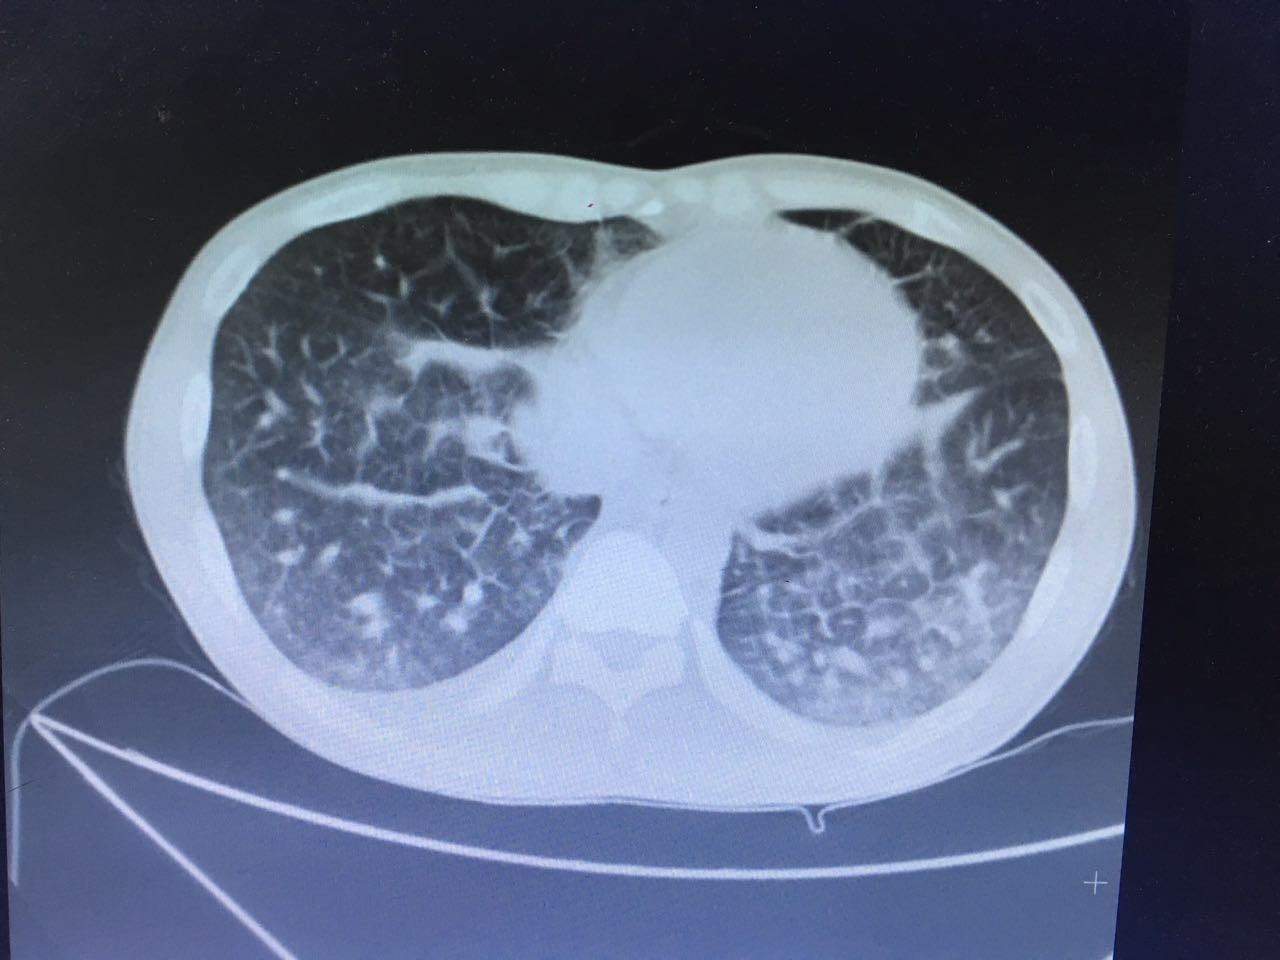

第二天,肺部CT做下来,我们傻了,和胸片差别太大了!从中下肺开始,那是大片的阴影啊!CT提示为间质性肺炎,找放射科主任读片,认为不符合肺结核、肺癌的表现(图1-3.)马上再回到病床前再次确认——没有吸烟史、没有慢性咳嗽史、没有咯血、没有盗汗史。再查体:浅表淋巴结确实不肿大,双肺呼吸音可以算略粗糙也可以算清晰。——这么这么静默的肺部体征,这么这么差的影像学结果,马上补查肿瘤标志物和自身免疫全套吧!

图1

图2

图3